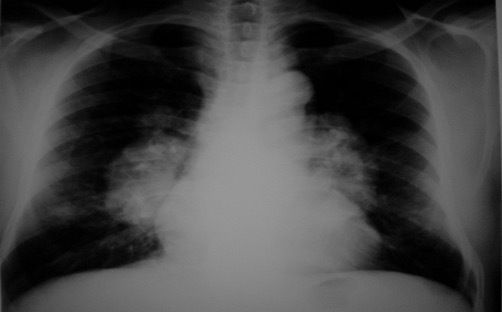

What features are seen on this CXR? What is the likely diagnosis?

hyperexpanded + flattened diaphragm

COPD